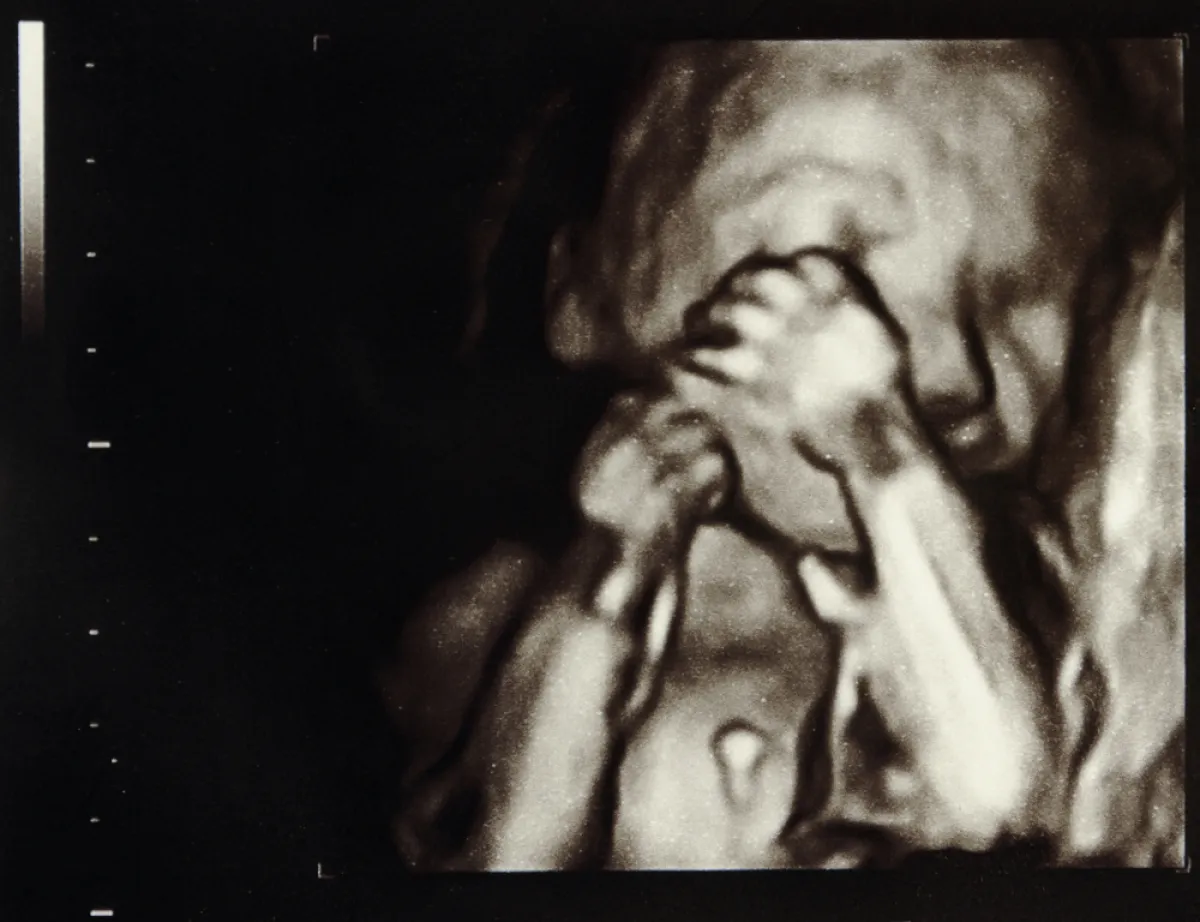

يبدأ الجنين في الاستجابة للأصوات خارج الرحم، ويعبر عن ذلك بحركاته وركلاته.

قبل ذلك تكون حركاته مثل رفرفة أجنحة الفراشة نظراً لصغر حجمه.